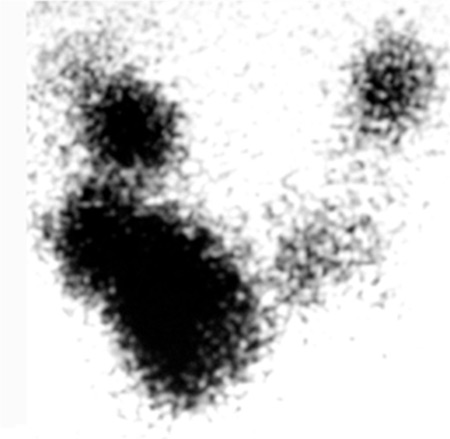

Nódulo tireoidiano hiperfuncionante suprimindo a glândula contralateral na cintilografia de tireoide (SSN = incisura jugular)

Arem R. Recurrent transient thyrotoxicosis in multinodular goitre. Postgrad Med J. 1990;66:54-56